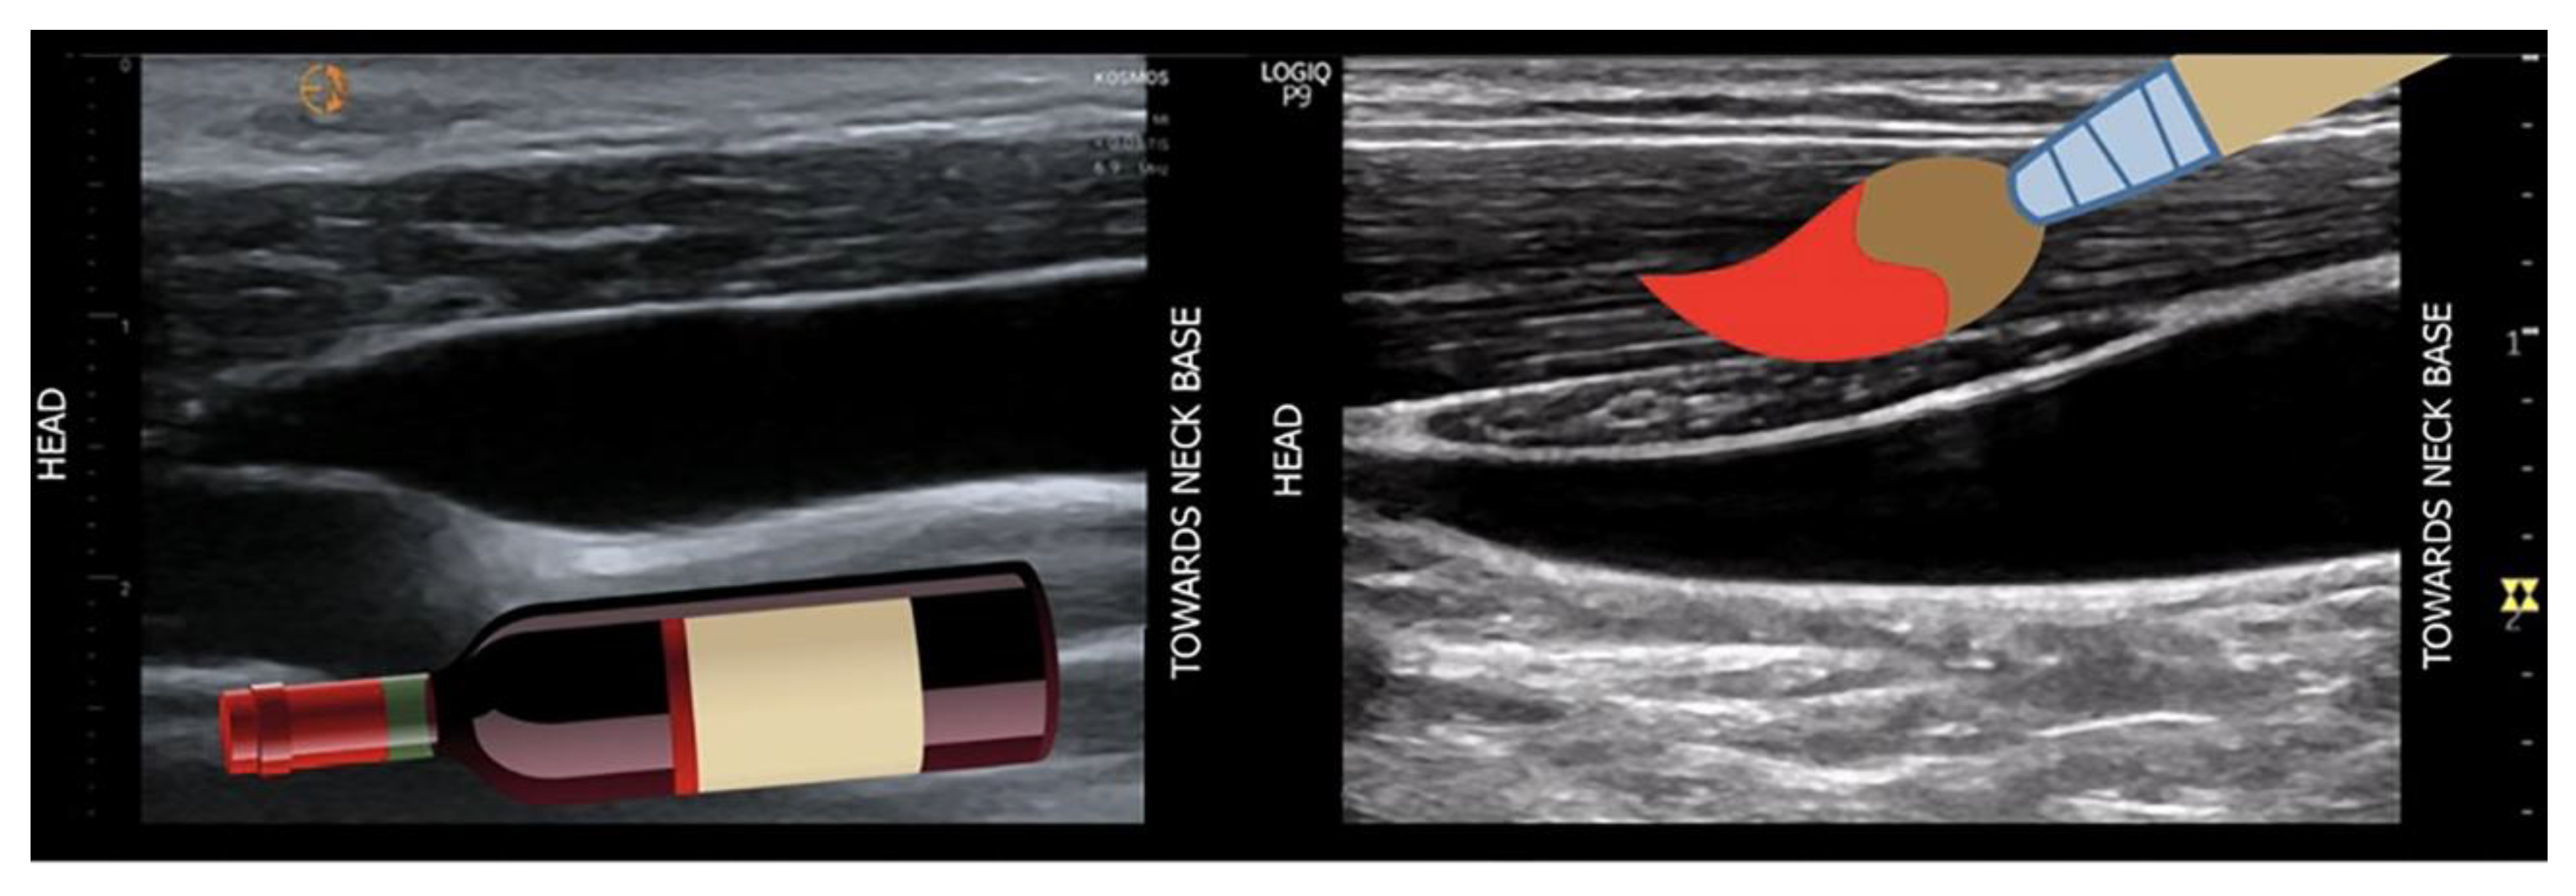

3.1. Ultrasound Measurements of Splanchnic Circulation

3.1.1. B-MODE:

Bowel-Wall Thickening

Venous Congestion

3.1.2. Ecocolordoppler and Spectral Velocity Variations:

PORTAL VEIN: